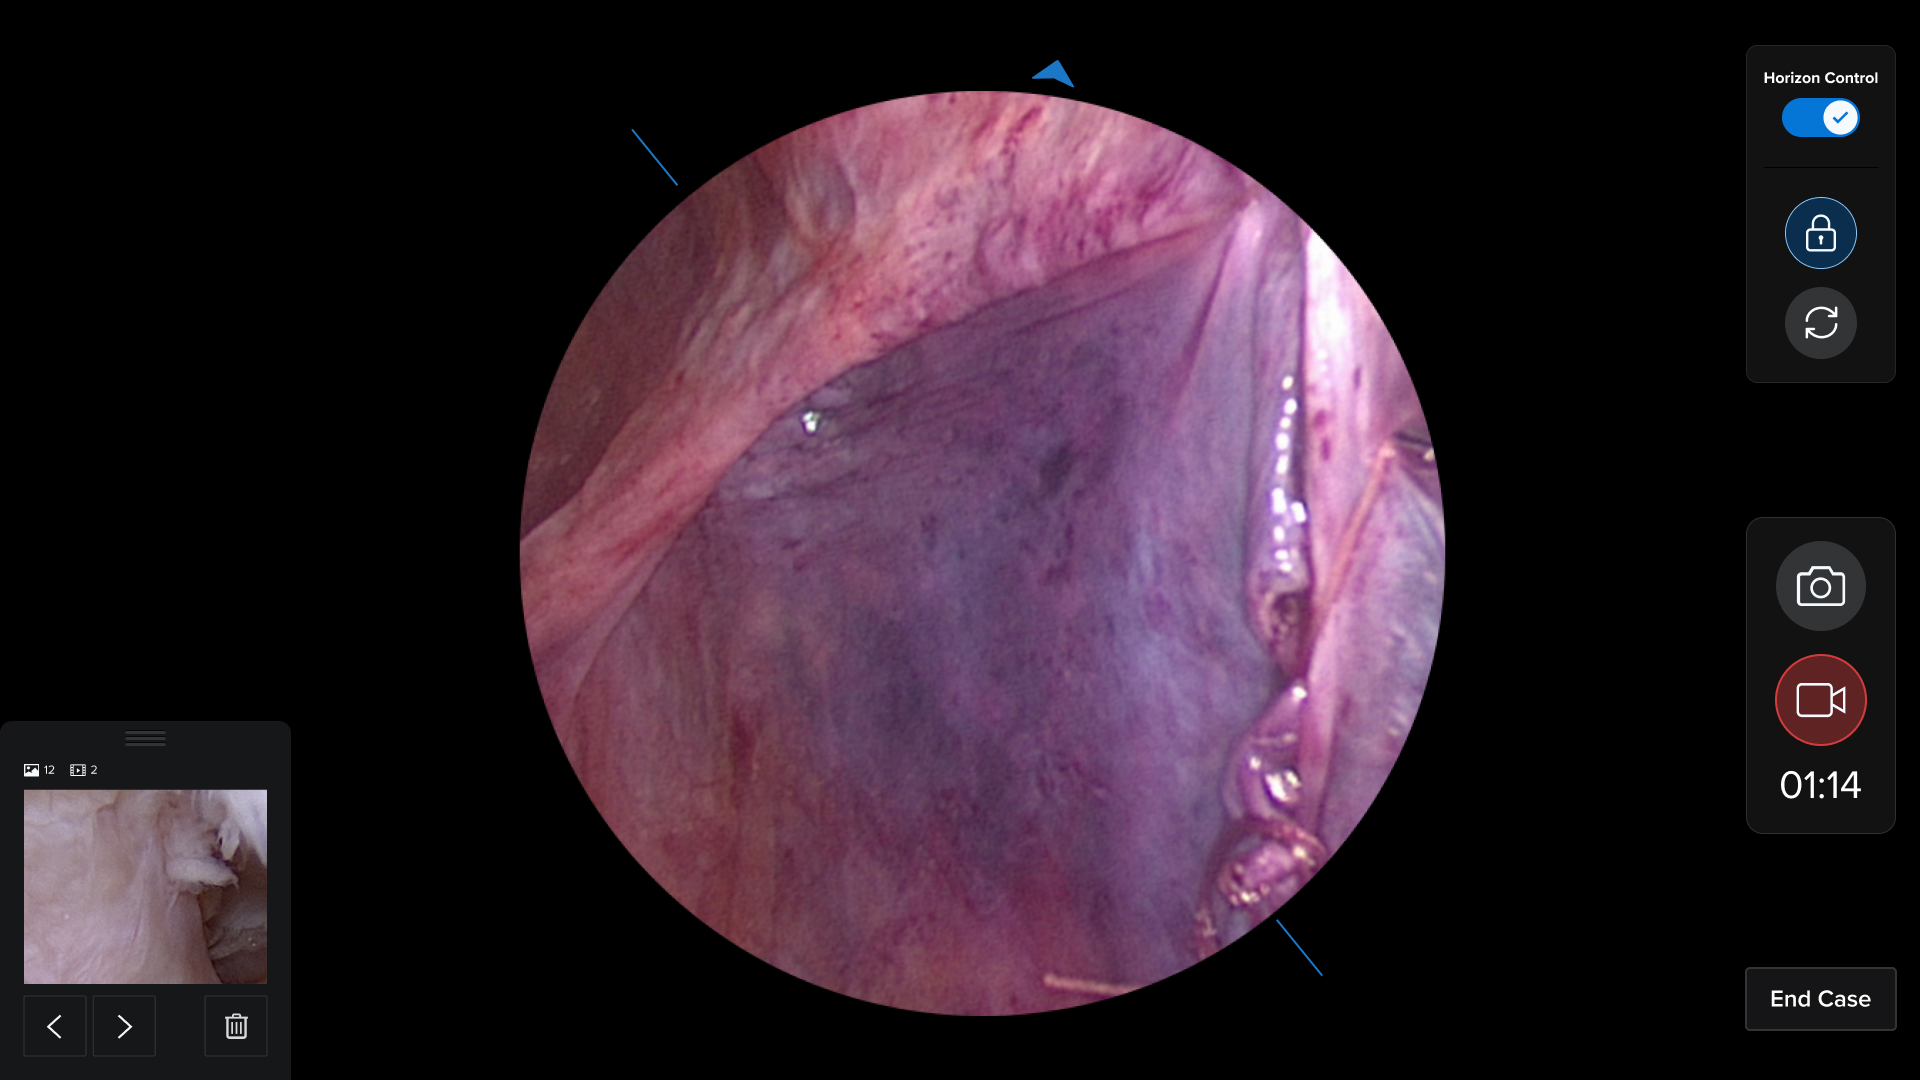

Watch how I brought digital designs to life with real medical hardware

HUD Design: Surgery-Ready Interfaces

Operating rooms aren't like offices. I designed interfaces specifically for heads-up displays, considering lighting, distance, and the critical nature of surgical procedures.